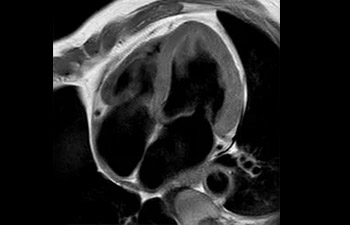

Hersenlaesie

met Compressed SENSE

Bekken vrouw met myoom

met Compressed SENSE